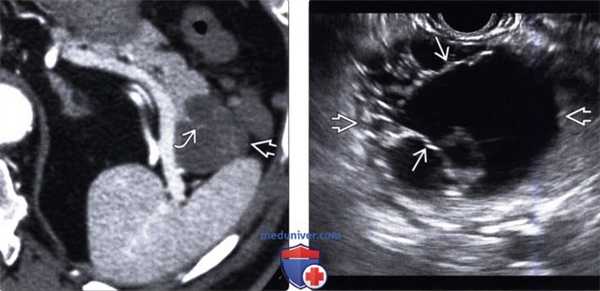

2. УЗИ при внутрипротоковой папиллярной муцинозной опухоли поджелудочной железы:

• Опухоль главного панкреатического протока: расширенный проток может содержать источники низкоинтенсивных эхосигналов (муцин или интрамуральные узлы)

• Опухоль боковой ветви протока: анэхогенное или гипоэхогенное кистозное образование ± перегородки; может определяться соустье с протоком железы и его расширение

(Левый) На поперечном косом УЗ срезе брюшной полости определяется расширенный главный проток поджелудочной железы. Также видна верхняя брыжеечная вена.

(Правый) У этого же пациента при УЗИ брюшной полости в головке поджелудочной железы в каудальном направлении от главного протока железы выявлено прилегающее к нему многокамерное кистозное новообразование. (Левый) У этого же пациента при Т2-ВИ МРТ на аналогичной томограмме визуализируется тонкостенное тубулярное кистозное новообразование с криволинейным соустьем с главным протоком поджелудочной железы, что соответствует картине внутрипротоковой папиллярной муцинозной опухоли боковой ветви главного протока.

(Правый) При МР холангиопанкреатографии в режиме 3D-реконструкции лучше визуализируется соустье между кистозным новообразованием и главным протоком поджелудочной железы, что соответствует картине внутрипротоковой папиллярной муцинозной опухоли боковой ветви главного протока. Случайно выявлен длинная сегментарная стриктура общего желчного протока. (Левый) При УЗИ брюшной полости в головке/теле поджелудочной железы определяются множественные овальные и удлиненные кистозные новообразования. Также заметна селезеночная вена.

(Правый) При МРТ в режиме Т2 HASTE на корональной томограмме в теле поджелудочной железы лучше визуализируется удлиненное кистозное расширение боковой ветви протока и изогнутое соустье с расширенным главным протоком поджелудочной железы.